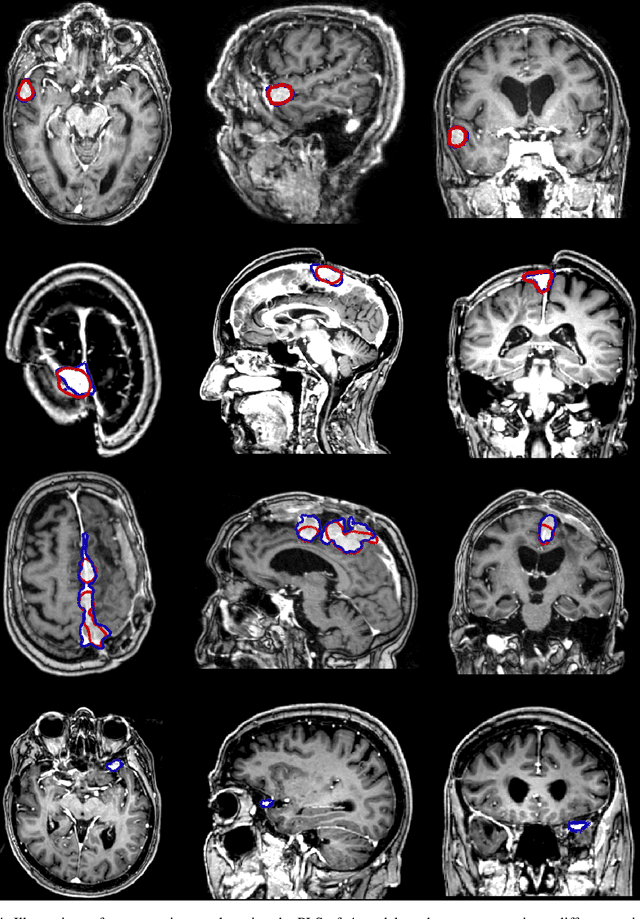

Abstract:Meningiomas are the most common type of primary brain tumor, accounting for approximately 30% of all brain tumors. A substantial number of these tumors are never surgically removed but rather monitored over time. Automatic and precise meningioma segmentation is therefore beneficial to enable reliable growth estimation and patient-specific treatment planning. In this study, we propose the inclusion of attention mechanisms over a U-Net architecture: (i) Attention-gated U-Net (AGUNet) and (ii) Dual Attention U-Net (DAUNet), using a 3D MRI volume as input. Attention has the potential to leverage the global context and identify features' relationships across the entire volume. To limit spatial resolution degradation and loss of detail inherent to encoder-decoder architectures, we studied the impact of multi-scale input and deep supervision components. The proposed architectures are trainable end-to-end and each concept can be seamlessly disabled for ablation studies. The validation studies were performed using a 5-fold cross validation over 600 T1-weighted MRI volumes from St. Olavs University Hospital, Trondheim, Norway. For the best performing architecture, an average Dice score of 81.6% was reached for an F1-score of 95.6%. With an almost perfect precision of 98%, meningiomas smaller than 3ml were occasionally missed hence reaching an overall recall of 93%. Leveraging global context from a 3D MRI volume provided the best performances, even if the native volume resolution could not be processed directly. Overall, near-perfect detection was achieved for meningiomas larger than 3ml which is relevant for clinical use. In the future, the use of multi-scale designs and refinement networks should be further investigated to improve the performance. A larger number of cases with meningiomas below 3ml might also be needed to improve the performance for the smallest tumors.

Abstract:Automatic and consistent meningioma segmentation in T1-weighted MRI volumes and corresponding volumetric assessment is of use for diagnosis, treatment planning, and tumor growth evaluation. In this paper, we optimized the segmentation and processing speed performances using a large number of both surgically treated meningiomas and untreated meningiomas followed at the outpatient clinic. We studied two different 3D neural network architectures: (i) a simple encoder-decoder similar to a 3D U-Net, and (ii) a lightweight multi-scale architecture (PLS-Net). In addition, we studied the impact of different training schemes. For the validation studies, we used 698 T1-weighted MR volumes from St. Olav University Hospital, Trondheim, Norway. The models were evaluated in terms of detection accuracy, segmentation accuracy and training/inference speed. While both architectures reached a similar Dice score of 70% on average, the PLS-Net was more accurate with an F1-score of up to 88%. The highest accuracy was achieved for the largest meningiomas. Speed-wise, the PLS-Net architecture tended to converge in about 50 hours while 130 hours were necessary for U-Net. Inference with PLS-Net takes less than a second on GPU and about 15 seconds on CPU. Overall, with the use of mixed precision training, it was possible to train competitive segmentation models in a relatively short amount of time using the lightweight PLS-Net architecture. In the future, the focus should be brought toward the segmentation of small meningiomas (less than 2ml) to improve clinical relevance for automatic and early diagnosis as well as speed of growth estimates.